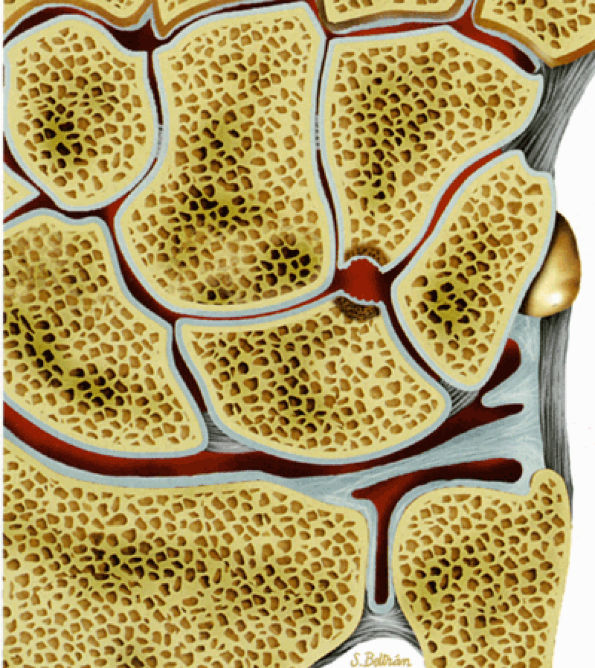

At the site of the radiolunate articulation, the distal articular surfaces of the radius and ulna are usually at the same level (i.e., neutral ulnar variance). Alternatively, the ulna may be relatively long (positive ulnar variance), leading to an ulnar abutment syndrome, or relatively short (negative ulnar variance), as is often seen in Kienböck's disease. The distal radius forms two facets that articulate with the scaphoid and lunate of the proximal carpal row. This articulation of the proximal pole of the scaphoid in the scaphoid fossa is quite congruent, and even a small degree of malrotation of the scaphoid may cause incongruent loading of the articular cartilage and subsequent degeneration (such as that which accompanies a SLAC wrist, as described by Watson and Ryu37). The lunate facet commonly becomes incongruent following distal radius fractures, especially die-punch-type fractures. The interosseous ligaments join the proximal carpal bones at their proximal edges.36